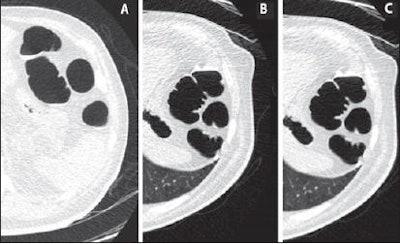

| Axial CTC images for comparison of standard versus low-dose ASIR technique at the level of splenic flexure. Above (A-C), 2D axial images -- supine image using standard-dose CTC with 50 mAs and 0% ASIR (A), prone image using 25 mAs and 0% ASIR (B), and prone image using 25 mAs and 40% ASIR (C) -- show ASIR reduces noise artifact to produce improved image. Below (D-G), 3D axial images without and with ASIR -- 50 mAs without ASIR (D), 50 mAs with ASIR (E), 25 mAs without ASIR (F), and 25 mAs with ASIR (G) -- show addition of ASIR reduces image artifact (mucosal nodularity and endoluminal floaters) with both dose settings. Images D and G are comparable despite reduced dose (2.1 versus 4.2 volume CT dose index). Images republished with permission of the American Roentgen Ray Society. |